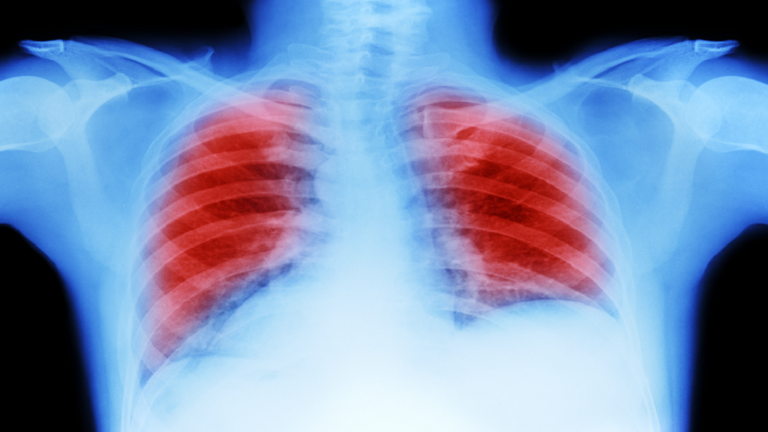

سرطان الرئة: علامة "العلم الأحمر" التي تظهر عند السعال!